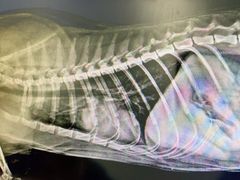

• 荔康动物医院(康王北路店)

• -荔康动物医院(康王北路店)